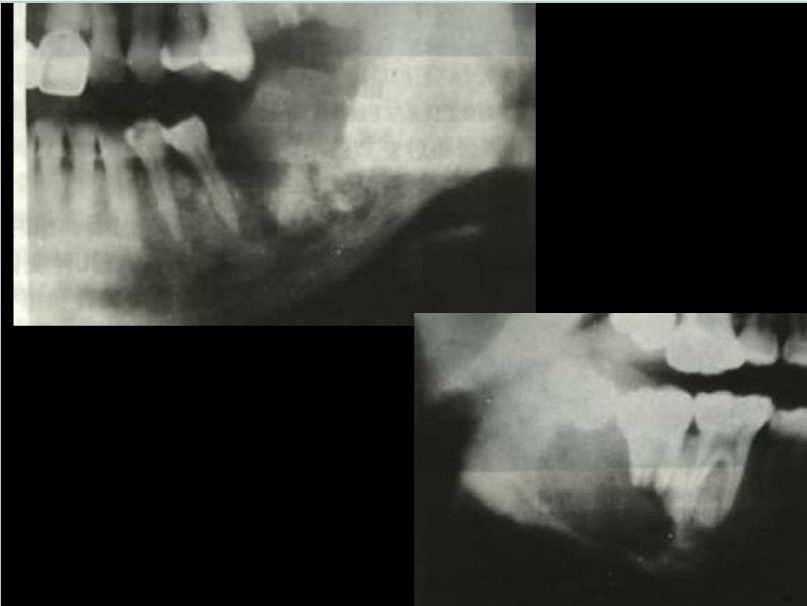

口腔頜面外科 影像技術(shù)